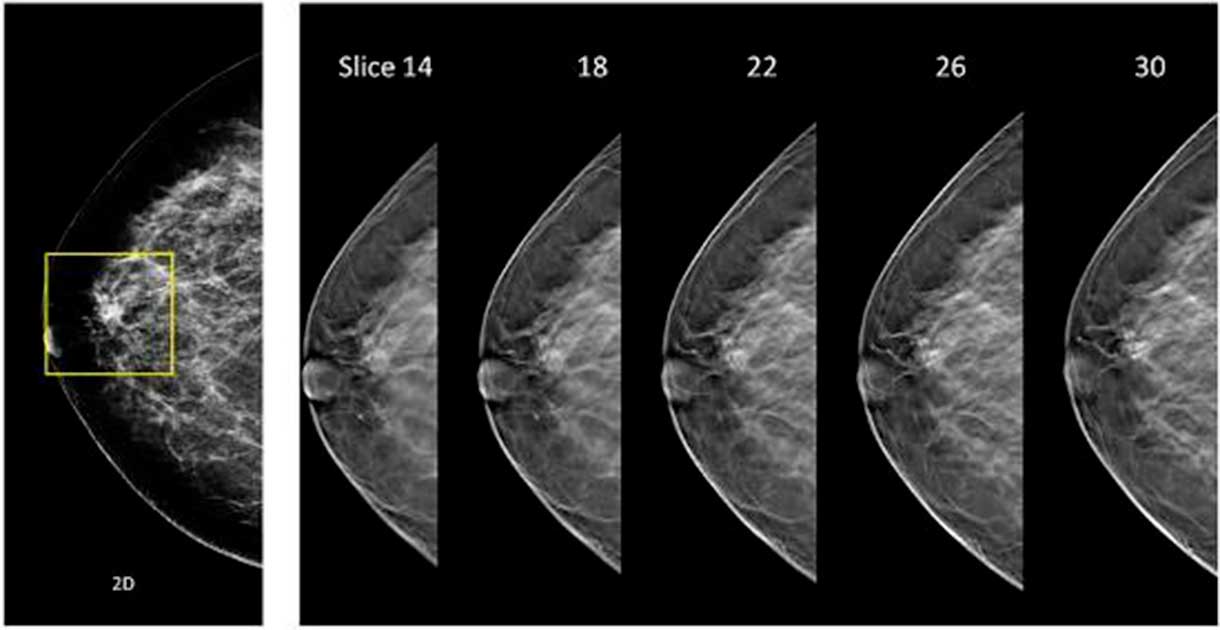

A evolução da mamografia tradicional, conhecida como tomossíntese ou mamografia 3D, garante resultados mais precisos e detecção precoce - também em mamas densas, aquelas que são mais difíceis de diagnosticar.

No Brasil, a tecnologia é oferecida pela Hologic por meio dos equipamentos Selenia Dimensions e 3Dimensions, que permitem que os médicos examinem o tecido mamário camada por camada. Então, em vez de visualizar a mama em uma imagem única e plana, como na mamografia 2D convencional, é possível ter uma visão mais detalhada e precisa.

“Na mamografia 3D o aparelho gera múltiplas imagens que permitem identificar nódulos com menos de 1cm. Se tiver alguma área suspeita e que não aparecia na mamografia convencional, o exame 3D irá mostrar. Mais de 200 estudos clínicos demonstraram que com o uso desta tecnologia os médicos são capazes de procurar por câncer de mama com muito mais precisão, independentemente da idade ou da densidade das mamas da paciente”, comenta Dra. Vivian Schivartche, médica radiologista especialista no diagnóstico de câncer de mama do CDB Premium.